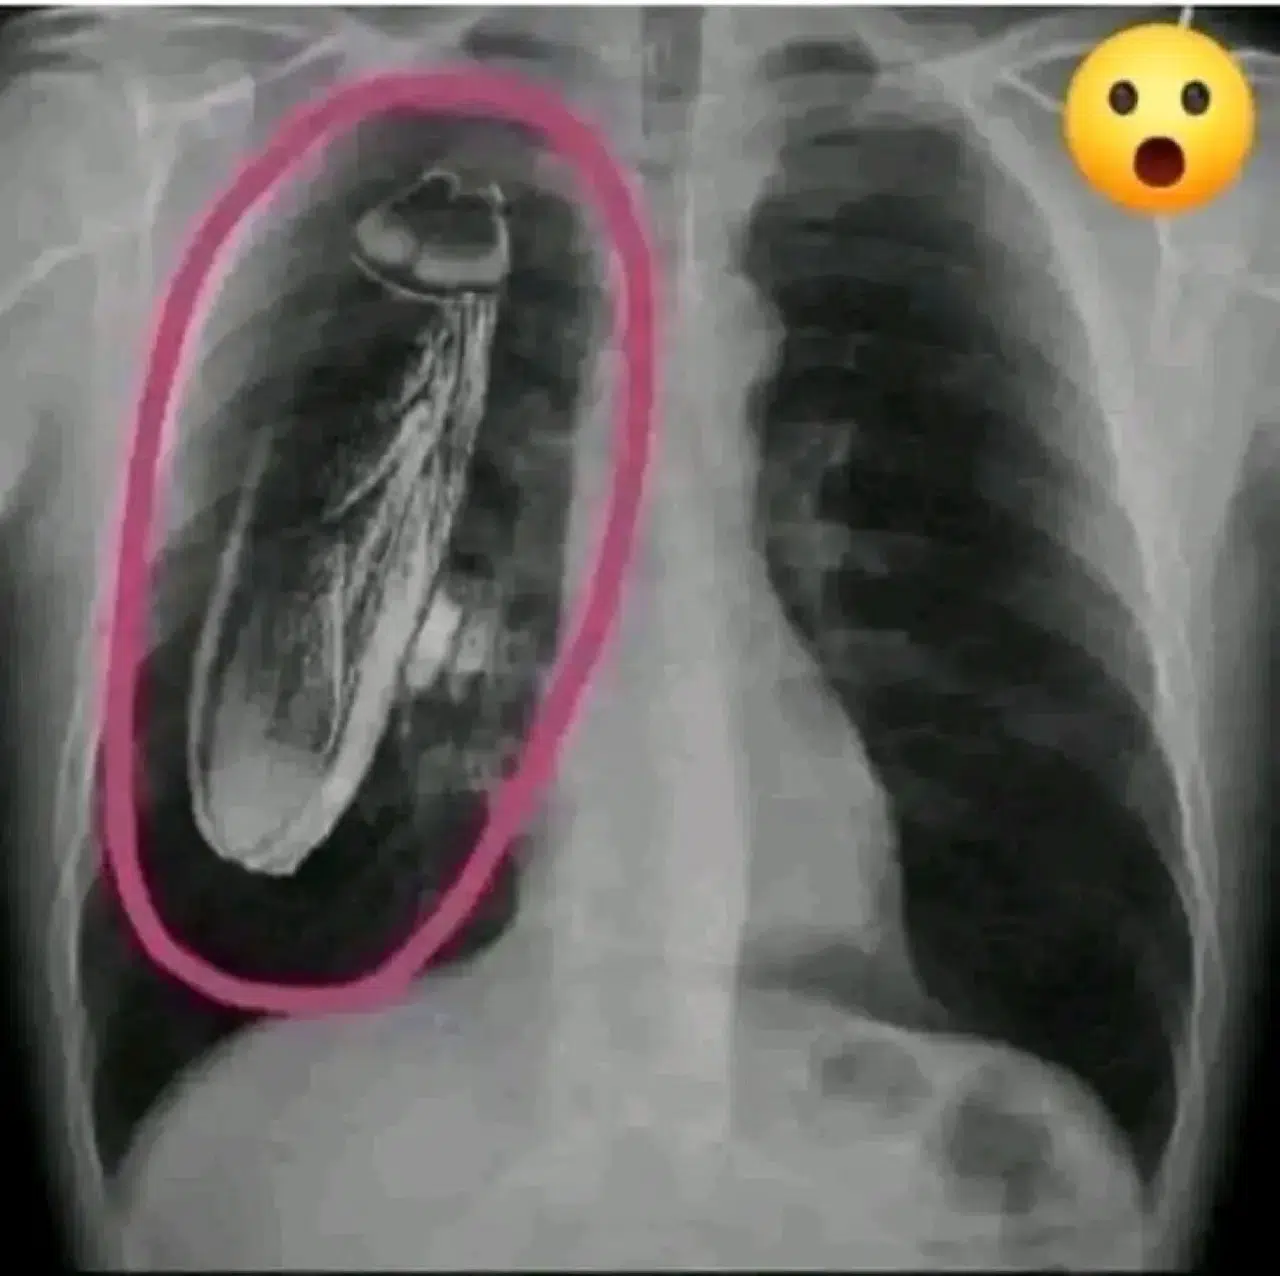

Kenya'daki bir devlet hastanesinde bir hastanın röntgeni çekildi ve göğsünde canlı bir hamamböceği olduğu söylendi. "Tedavi için Singapur'a gitmeniz gerekecek."

Hasta Singapur'a gitti ve hamamböceğinin göğsünde değil, röntgen makinesinin içinde olduğu söylendi.